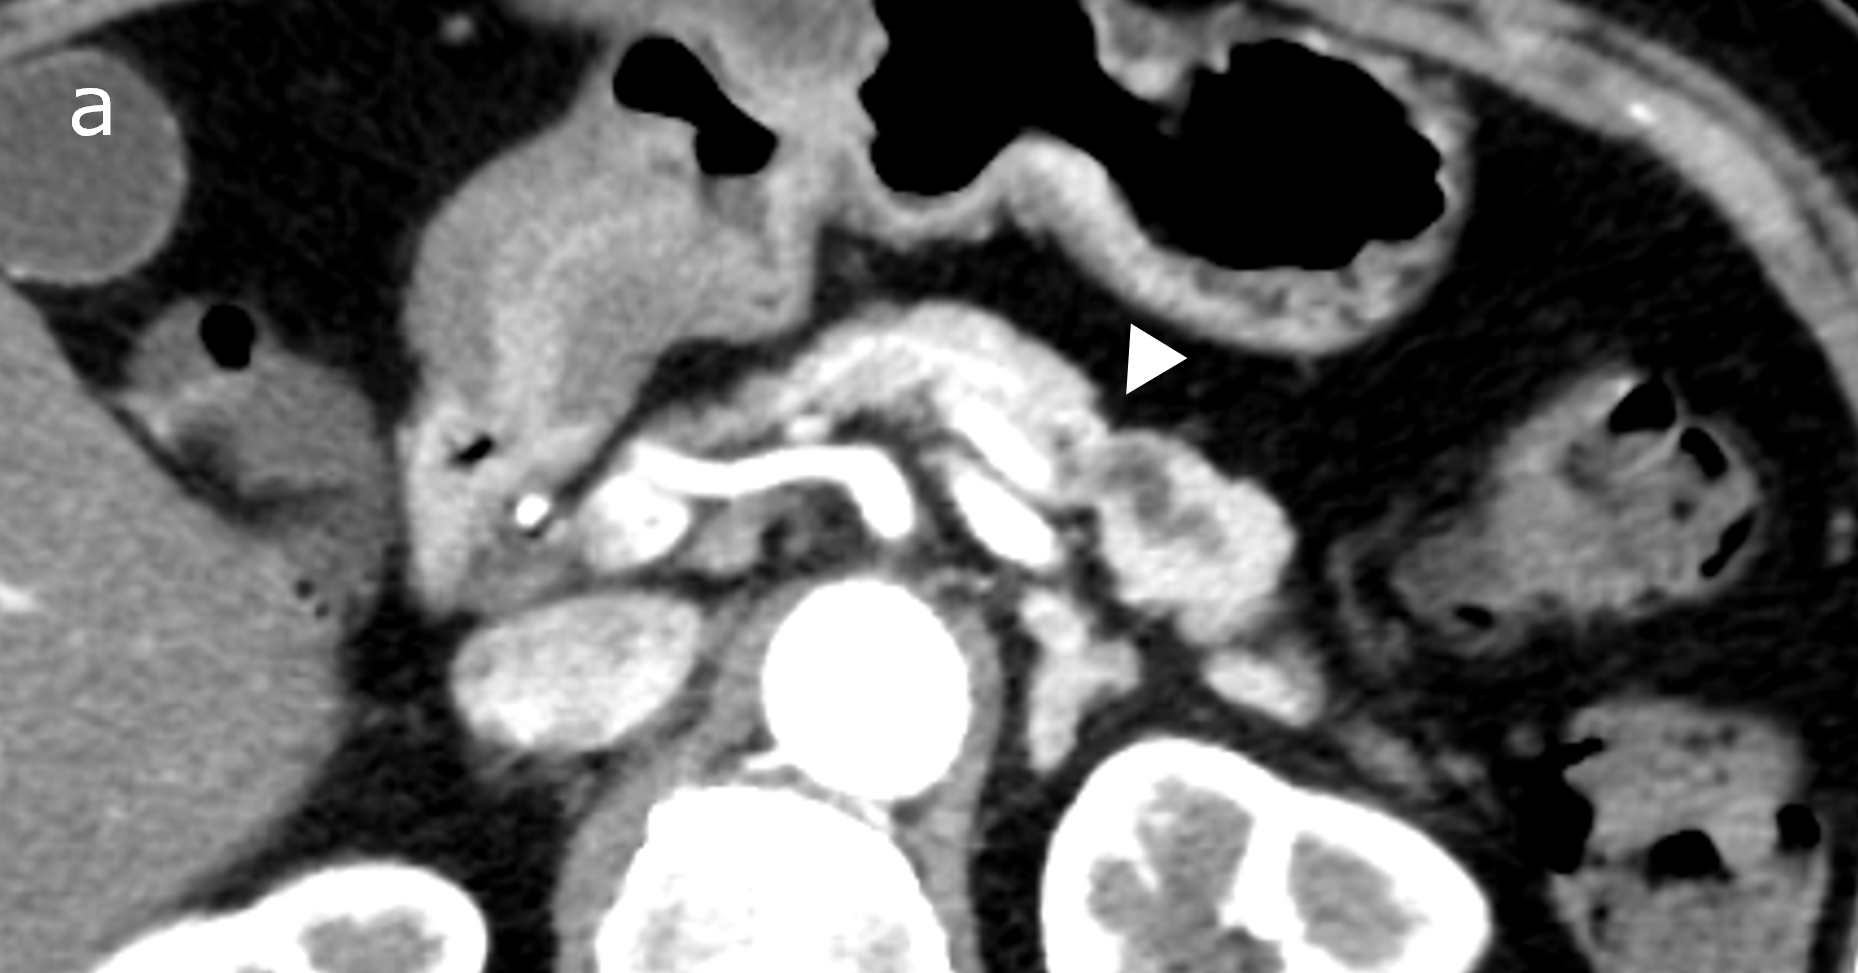

図3(a):CT(a)では、白矢印の部分に膵の萎縮を認める。

図3(b):MRI(MRCP)(b)では膵尾部の主膵管が白矢印の部位から拡張している。

図3(c):EUS(c)では、主膵管の拡張がはじまる部位の周囲に淡い低エコー領域(白矢印)を認める。以上から、強く早期の膵癌を疑い、複数回の膵液細胞診を行い腺癌と診断、手術ののち膵上皮内癌と最終診断された。